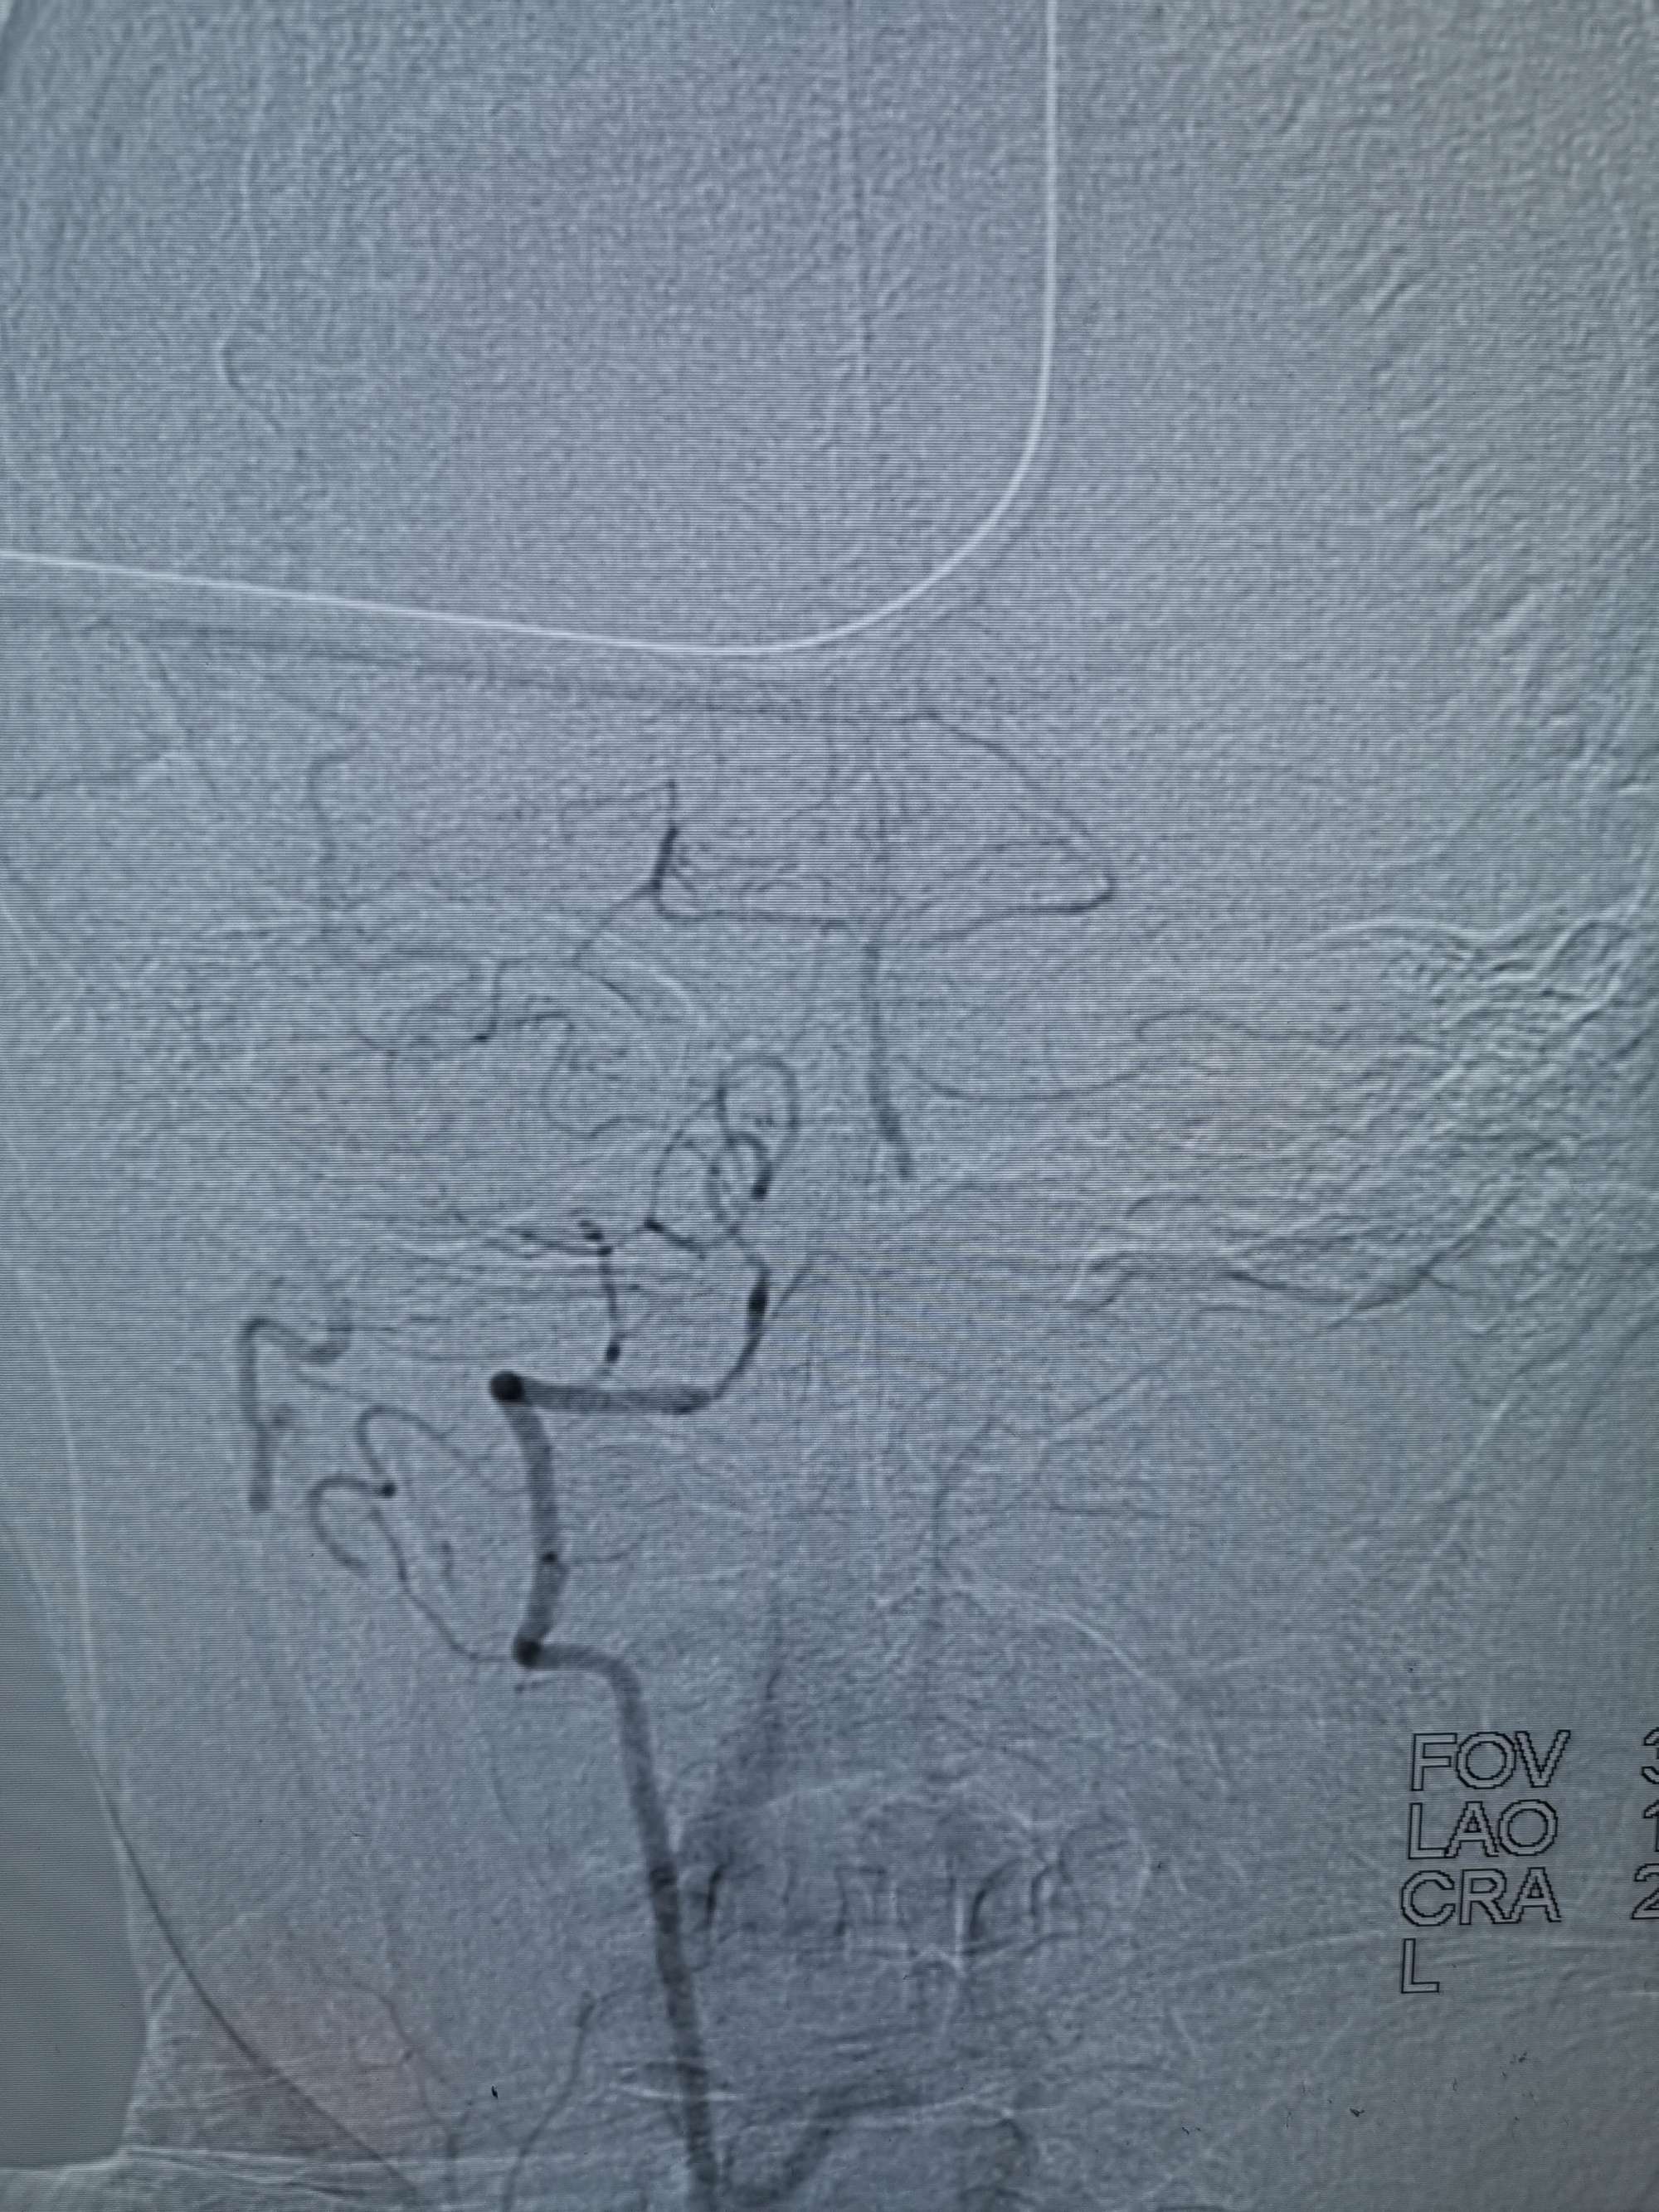

入院造影影像

术前再次造影评估

右侧椎动脉穿支供血及左侧PICA供血较入院时略有改善,但改善不明显。故按计划行左侧椎动脉再通术